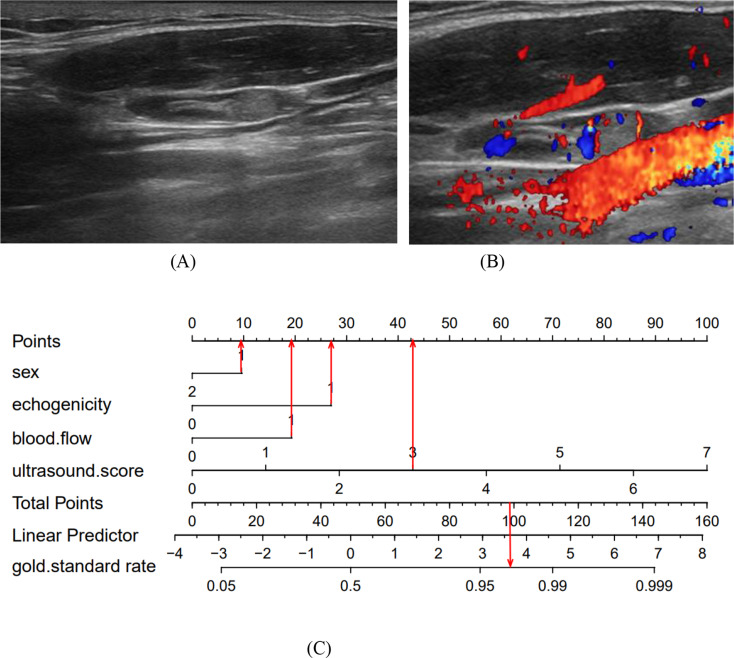

Results: In this study, factors such as age, sex, lymph node length, thickness, aspect ratio, shape, hilum status, echogenicity, microcalcification, cystic necrosis, blood flow pattern, and the ultrasonic score were included in the analysis. The ultrasound score had the highest (AUC = 0.914, 95% confidence interval [CI]: 0.880-0.950), with an optimal cutoff value of 2.5. A score of 3 or higher had a diagnostic sensitivity for CLNM of 81.1%, specificity of 85.2%, positive predictive value (PPV) of 83.1%, negative predictive value (NPV) of 83.4%, and Kappa value of 0.664. Subsequent LASSO regression analysis identified sex, hyperechogenicity, peripheral disordered blood flow, and the ultrasonic score as independent predictors of CLNM, which were incorporated into a logistic regression-based predictive nomogram. The model exhibited strong discriminatory performance in both the training set (AUC = 0.933, 95% CI: 0.820-0.910) and the test set (AUC = 0.958, 95% CI: 0.790-0.890) for distinguishing PTC with and without CLNM. Furthermore, calibration curves and decision curve analysis (DCA) confirmed the model's good fit and favorable clinical net benefit.

Conclusion: The ultrasonic scoring method and the Nomogram have significant clinical utility in the preoperative assessment of CLNM in PTC, reducing unnecessary FNA procedures, and are simple and practical for clinical application.